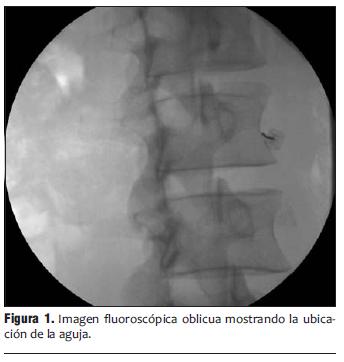

Se ubicó una aguja a nivel del tercio inferior de L2, una segunda aguja en el tercio superior de L3 y la tercera aguja en el tercio medio de L4 (figura 4).